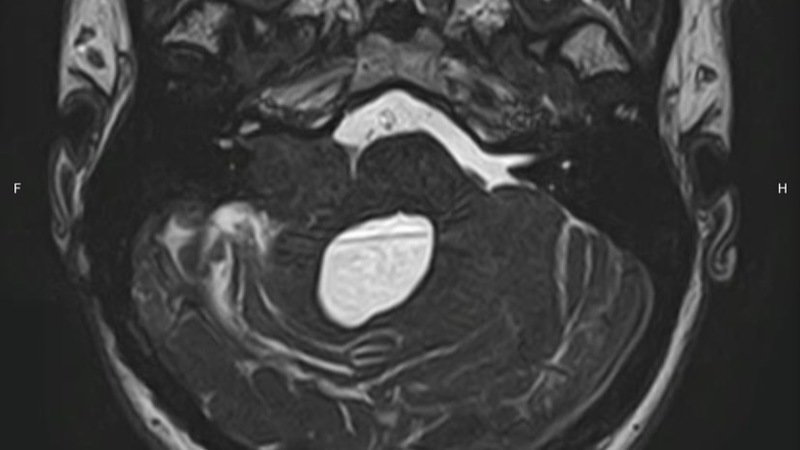

Hace 4 años me descubrieron un tumor, el cual comprime mi cerebro y poco a poco ha cambiado radicalmente mi vida. En un inicio, solo padecía de migrañas terribles, pero hoy en día he perdido gravemente mi audición y mi movilidad, lo que no me permite trabajar. En estos 4 años he tenido muchas luchas con mi EPS Salud Total, han habido tutelas, pero en general el proceso médico se ha llevado a cabo: más del 80% del tumor fue retirado y se me trató con radioterapia para evitar que siguiera creciendo.